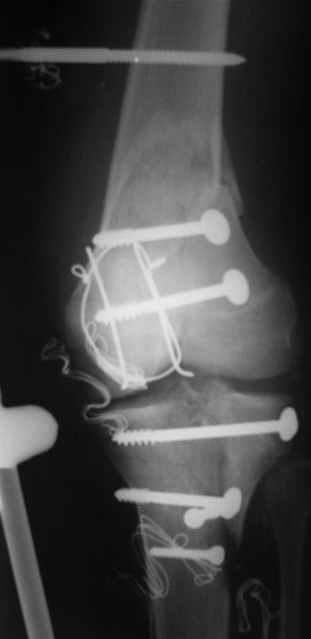

Спасибо за рекомендации. Сегодня взял больного на очередную хирургическую обработку и внешнюю фиксацию, картинки в приложении. При обработке опять иссекал ушибленные неркотизированные мышцы, частично кожный лоскут (явные признаки демаркации). связка надколенника разволокнена и выглядит едва ли жизнеспособной, пришлось частично убрать *лохмотья*.

Беда в том, что иссекая нежизнеспособные ткани происходит обнажение кости (рефиксироанная бугристость) м медиального края надколенника. Образовался обширный дефект наружной группы мышц. Литров 10 стерильного физ раствора извел на промывание раны. Заказал снимки, завтра поглядим.

Картинки по порядку: вид раны после первичной обработки, на следующий день и сегодня после

повторной обработки и внешней фиксации.

Рентген дошлю по мере готовности.